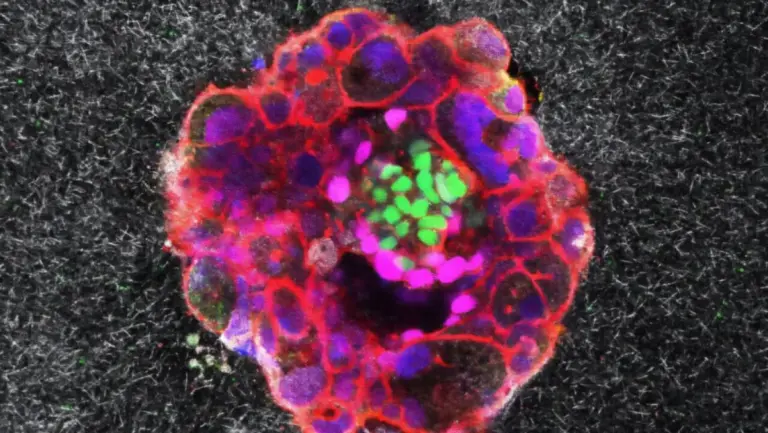

Onderzoekers van het Max Planck-Institut gebruikten een geavanceerde beeldvormingstechniek op follikels van muizen, die buiten het lichaam in een petrischaaltje groeiden. Ze werden gestimuleerd met specifieke hormonen die ovulatie in gang zetten. Met deze methode konden ze het ontstaan en de vrijlating van een eicel stap voor stap filmen, zoals nooit tevoren.

- Fase 1 – Groei van het follikel: Het meest rijpe follikel groeit binnen acht uur bijna twee keer zo groot. Dit komt door de productie van hyaluronzuur, dat zorgt voor instroom van vocht.

- Fase 2 – Samentrekking van de spierlaag: De buitenste spiercellen trekken samen en bereiden de ‘lancering’ van de eicel voor.

- Fase 3 – Vrijlating van de eicel: Uiteindelijk wordt de eicel krachtig naar buiten gestoten en komt in het laboratoriumschaaltje terecht. Precies deze fase is nu schitterend vastgelegd op video.